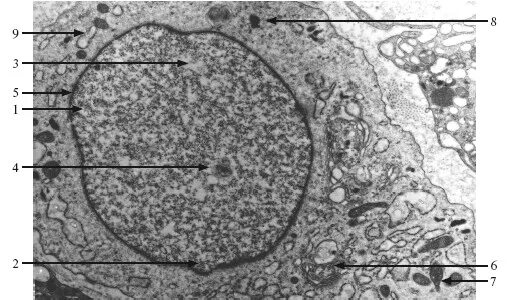

Содержит хроматин сливается с лизосомами